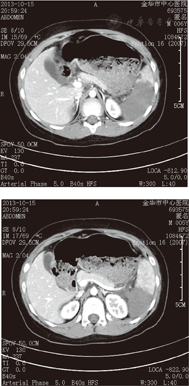

本组18例患儿,其中男10例,女8例,年龄2.5~12.0岁,平均年龄6.9岁。致伤原因:交通事故14例,高处坠落4例。伤后至入院时间最短45 min,最长1 d,平均住院时间21 d;均有腹部或左季肋区外伤史,经增强CT检查确诊,按我国目前4级法:18例患儿均为Ⅲ级外伤性脾破裂。其中1例患儿的增强CT结果见图1。

行保守治疗的18例Ⅲ级外伤性脾破裂患儿,1例中转开腹,17例保守治疗成功,均治愈出院,无死亡病例。住院时间为18~25 d,平均21 d。所有患儿于出院前均行超声和(或)增强CT复查,对17例患儿进行随访,外伤后1个月复查CT提示脾破裂创伤恢复良好,6个月后复查CT提示脾脏基本愈合。随访时间最短6个月,最长3年,均未发生并发症,CT检查显示肝脏形态结构基本正常。